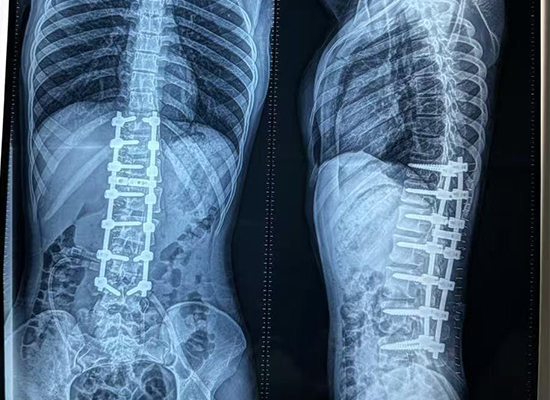

L'imagerie postopératoire a démontré :

Amélioration significative de l'alignement de la colonne vertébrale

Courbure réduite et proéminence des côtes

Épaules et tronc équilibrés

Cliniquement, Raisa a montré :

État neurologique stable

Contrôle de la douleur satisfaisant

Retour progressif à la position debout et à la marche avec appui

Amélioration de la posture et de l’apparence cosmétique

Sous un suivi étroit, le patient a continué à se rétablir en douceur et les premiers résultats suggèrent un pronostic favorable à long terme pour l'équilibre de la colonne vertébrale et la qualité de vie.